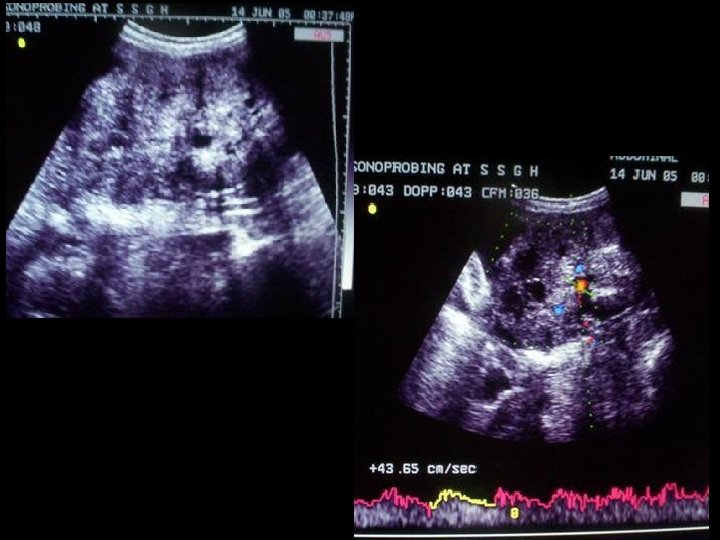

Tip-of-iceberg-sign : produce by the mixture of matted hair & sebum, which appears highly echogenic with ill defined acoustic shadowing that obscures the posterior wall of the lesion.

Dermoid mesh : multiple linear hyper echoic interfaces seen floating with in the cyst & these are the hair fibers. Lesion also shows dermoid plug & hair-fluid level

Axial US image shows Fat-fluid level

On USG • completely anechoic to hyperechoic appearance large cystic lesion. • highly echogenic dermoid plug (Rokitansky nodule), which is the solid element within the cyst that contains hair follicles, sebaceous glands, fat, and calcified elements. • Mixture of hair & sebum is highly echogenic and produces ill-defined acoustic shadowing which obscures the post wall of the lesion, k/a “ tip of the iceberg sign”. • Multiple linear hyperechoic interface seen floating within the cyst, k/a “dermoid mesh”. • Fat-fluid or hair-fluid level may be seen.

How to differentiate b/w benign & malignant GCT ? • preoperative diagnosis in differentiating malignancy from benign cystic teratomas of the ovary remains difficult • On color doppler, the malignant GCT shows prominent arterial flow within the fibrovascular septae • Sudden increase in size. • Malignant GCT is predominantly solid, with few focal anechoic areas, caused by hemorrhage or necrosis. • CT shows enhancement of these fibrovascular septae.